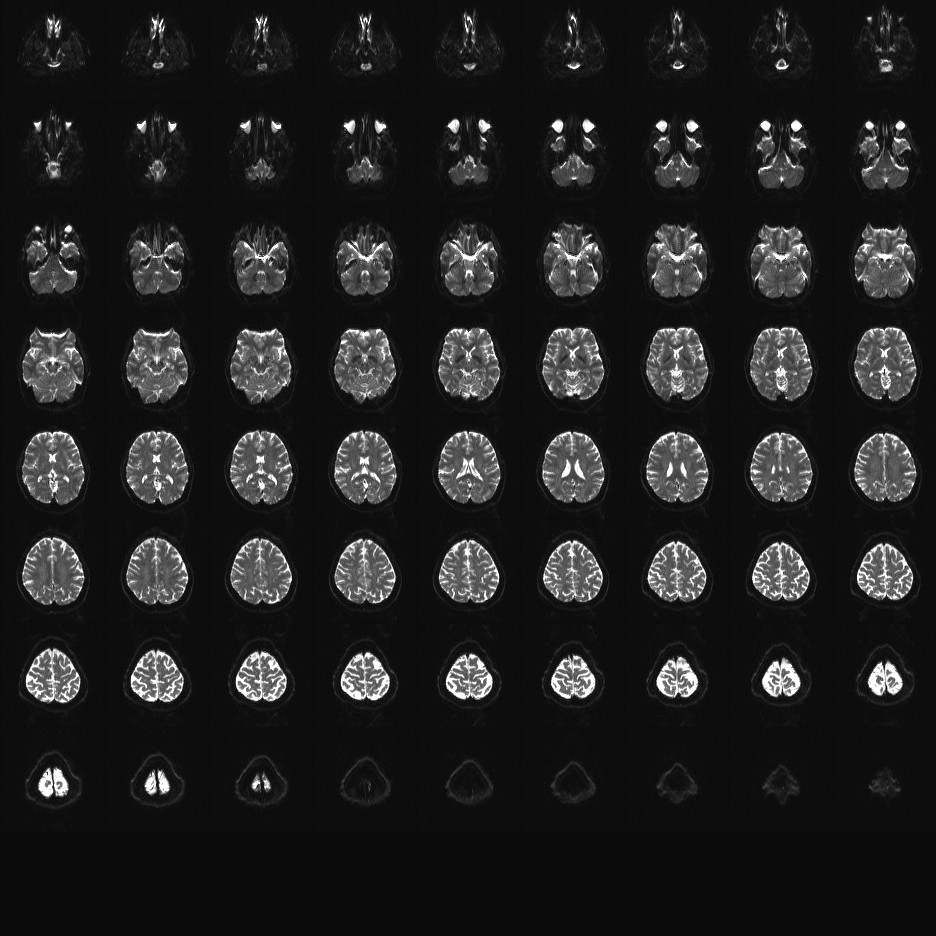

Multi-banded RF pulses can be used to accelerate volume coverage along the slice direction by simultaneously exciting and acquiring multiple slices and subsequently unaliasing them using parallel imaging principles and the spatial information available in multi-channel RF array coils.

This allows for a direct reduction in the volume TR by the number of simultaneously excited slices (i.e., the multiband (MB) factor or the slice acceleration factor).